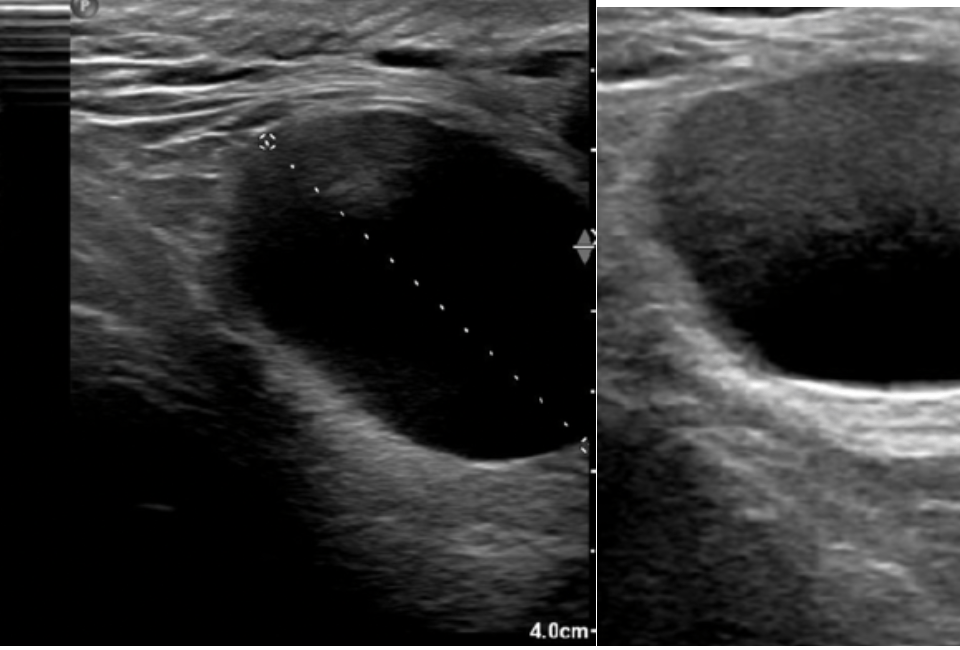

A novel use of Intracavity and intravenous CEUS: The delineation of hepatic abscess formation and conformation of catheter placement. [May 2019]